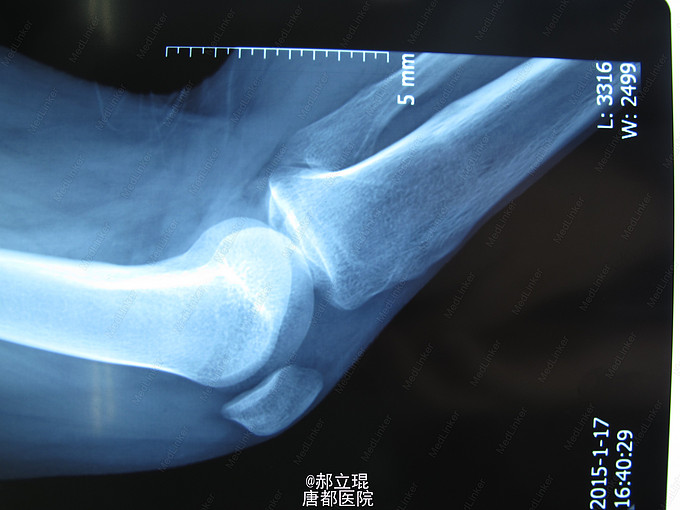

车祸伤致右膝疼痛,活动受限6小时入院。男性,30岁,6小时前车祸伤导致右膝膝关节疼痛,活动受限。全身情况良好。

专科情况:右膝肿胀,压痛阳性,活动受限,右下肢血运良好,无明显神经症状。抽屉试验阳性。侧方应力试验阴性。